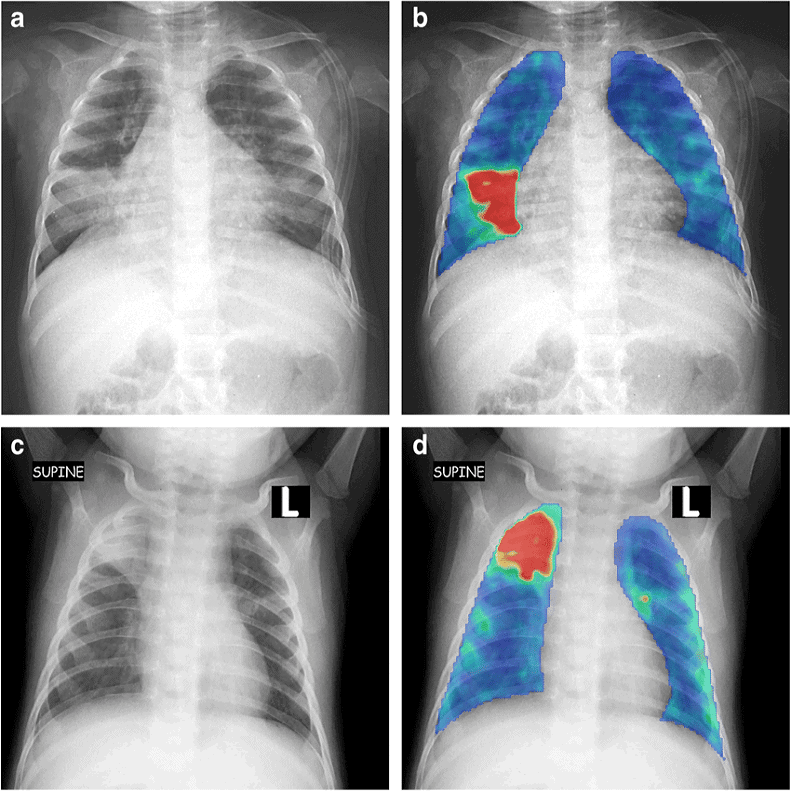

– Tùy thuộc kích thướng lỗ thông hình ảnh X-quang rất khác nhau

+ Lỗ thông nhỏ: hình ảnh X-quang thường bình thường.

+ Lô thông vừa: shunt trái – phải => giãn nhĩ trái và thất trái do tăng gánh tâm trương. Có thể giãn cung động mạch phổi, tăng lưu lượng tuần hoàn phổi chủ động.

+ Lỗ thông lớn: thất phải có thể giãn do tăng gánh tâm thu. Tăng kích thước động mạch phổi, giảm tuần hoàn phổi ngoại biên.

+ Động mạch chủ bình thường hoặc nhỏ do giảm cung lượng tim.

+ Bóng tim to nhưng khi đảo shunt có khuynh hướng thu nhỏ lại gần bình thường, thất phải dày làm mỏm tim hơi tròn và vênh lên cao trên vòm hoành.

+ Giãn cung động mạch phổi và có thể thấy giãn 2 gốc động mạch phổi.

+ Rốn phổi tăng đậm trong khi đó phế trường ngoại vi sáng hơn bình thường tạo hình ảnh cắt cụt điển hình trong phức hợp Eisenmenger.2. Thông liên nhĩ